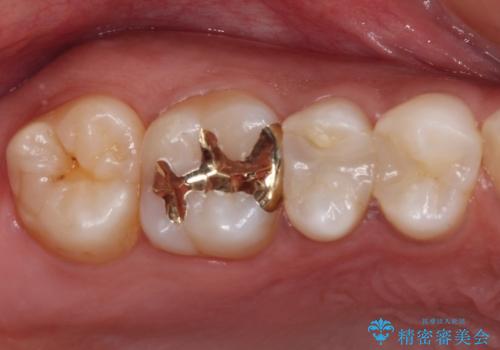

奥歯のむし歯をゴールドインレーで修復

奥で目立たないことから、虫歯の再発リスクが最も低く、咬合力による歯への負担も少ないゴールドインレー(PGAインレー、白金加金インレー)にて修復治療をすることとしました。

ゴールドインレーは銀歯のインレーやセラミックインレーと比べ、「技工操作の精度が高く、適合が著しく良い」というメリットがあります。特に上の奥歯は歯科医師の操作が行いにくいため、「適合の良さ」は再治療のリスクを防ぐ上でとても重要な要素となります。

上の奥歯は金属色が見えることもないため、審美的な問題は全くありません。